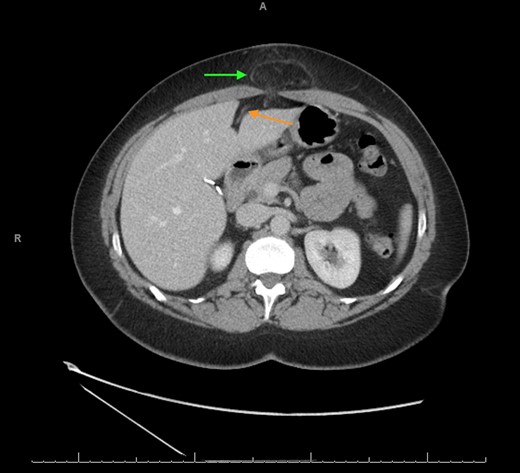

A computerized tomography (CT) scan demonstrated a chronic ventral hernia (Fig. 1) containing fat anterior to the left lobe of the liver which had marginally increased in size from a previous study done a year earlier. Through judicious use of analgesia, the hernia was successfully reduced. Two weeks later, the patient underwent a laparoscopic transabdominal pre-peritoneal (TAPP) mesh repair (Fig. 2). Laparoscopic visualization revealed, along with viable incarcerated omentum (Fig. 3), a falciform ligament hernia extending into the abdominal wall in the epigastrium.

CT scan axial view showing the falciform ligament hernia (green arrow) and the falciform ligament above the left lobe of the liver (orange arrow).